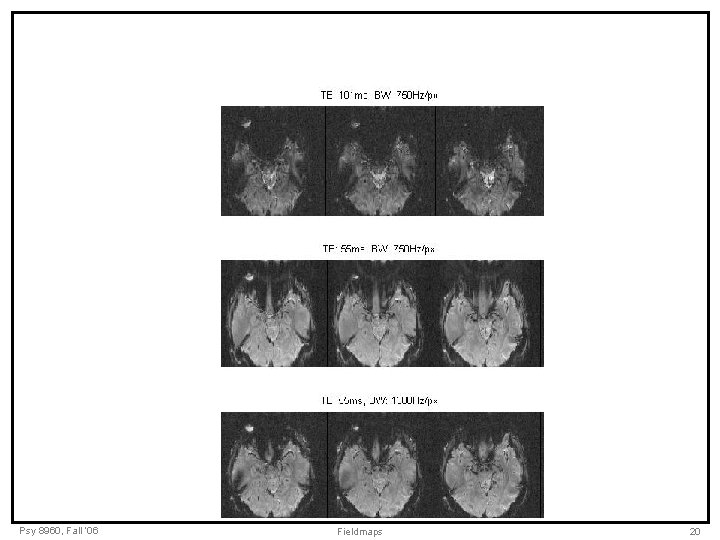

Psy 8960, Fall ‘ 06 Fieldmaps 20